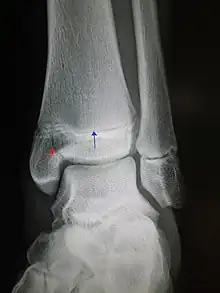

| An X-ray of the left ankle showing a Salter–Harris type III fracture of medial malleolus. Red arrow demonstrates fracture line while the blue arrow marks the growth plate. | |

- Type III – A fracture through growth plate and epiphysis, sparing the metaphysis:[9] 8% incidence